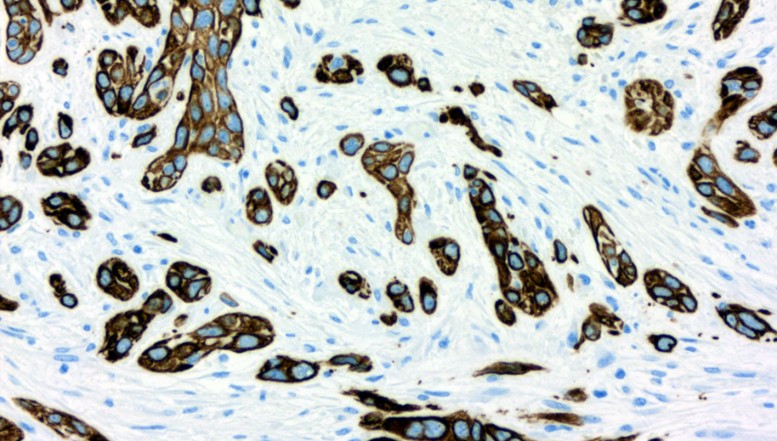

Artikelfoto Eine Keratin-7-Färbung macht den Bauchspeicheldrüsentumor sichtbar. Foto: Bosch Health Campus / S. Johnsen